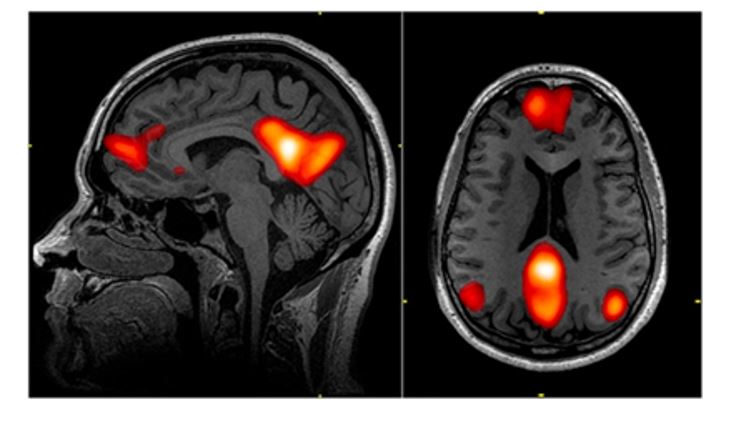

このデフォルトモードネットワークは、上の図にあるように、いくつかの脳領域が組み合わさってできている。

主な部分としては前頭前野の内側(内側前頭前野)と頭頂葉の内側(後帯状皮質・楔前部)、さらには頭頂葉外側の下半分(下頭頂小葉)だ。これらの領域が活動することで私達はぼんやりとすることができる。